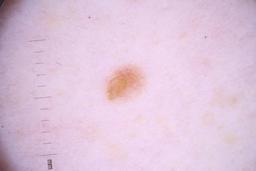

ISIC_4077341

Clinical

| Field | Value |

|---|---|

| acquisition_day | 1 |

| age_approx | 50 |

| anatom_site_1 | Trunk |

| anatom_site_2 | Anterior trunk |

| concomitant_biopsy | False |

| dermoscopic_type | contact non-polarized |

| diagnosis_1 | Benign |

| diagnosis_confirm_type | serial imaging showing no change |

| family_hx_mm | False |

| image_type | dermoscopic |

| lesion_id | IL_9238622 |

| patient_id | IP_1969685 |

| personal_hx_mm | True |

| sex | male |

Columns

Showing first 50 images.